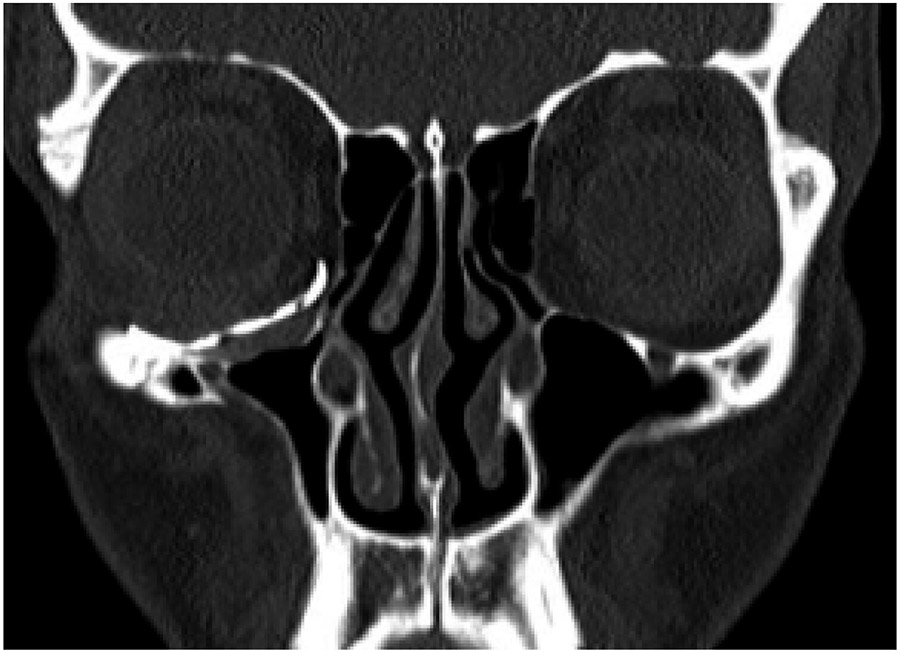

The patient reported a progressive, painless descent in her right eyeball over the last seven months, with no history of facial trauma or nasosinusal disorders. Clinical examination revealed enophthalmos, vertical dystopia and upper eyelid sulcus asymmetry (Fig. 1). Facial CT scan revealed a decreased right maxillary sinus volume with increased right orbital volume, downward displacement of orbital floor and collapse of the maxillary sinus (Fig. 2). Thus, a diagnosis of SSS was made based on the clinical and radiological findings.

The patient underwent a Caldwell-Luc approach and concurrent orbital floor reconstruction. A one-stage approach was chosen for a faster recovery and single surgery. Correction of enophthalmos and dystopia was performed using a patient-specific CAD/CAM implant (Fig. 3) assisted by intraoperative navigation and CT scan (Fig 4.). The 0.3mm orbital floor titanium plate was placed through a transconjunctival approach (Fig. 5). The patient was found to be complaint free and full recovered at 6th-month follow-up (Fig 1.).